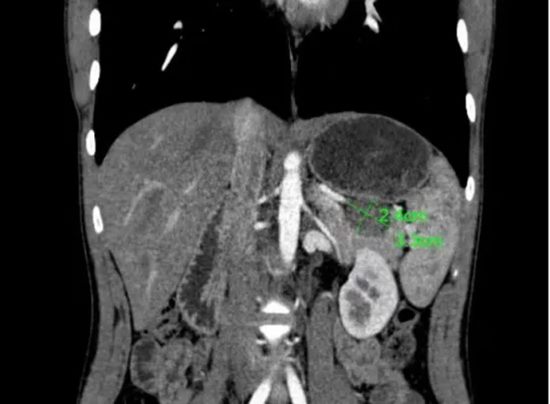

了解患者及家属的诉求后,陈艳军主任医师团队认真研读影像学资料,发现肿瘤位于胰腺尾部,紧邻脾门,与脾动脉、脾静脉关系密切。团队经过多方考量、反复讨论,最终决定为患者实施保留脾脏动静脉的保脾胰体尾切除术(Kimura手术)。